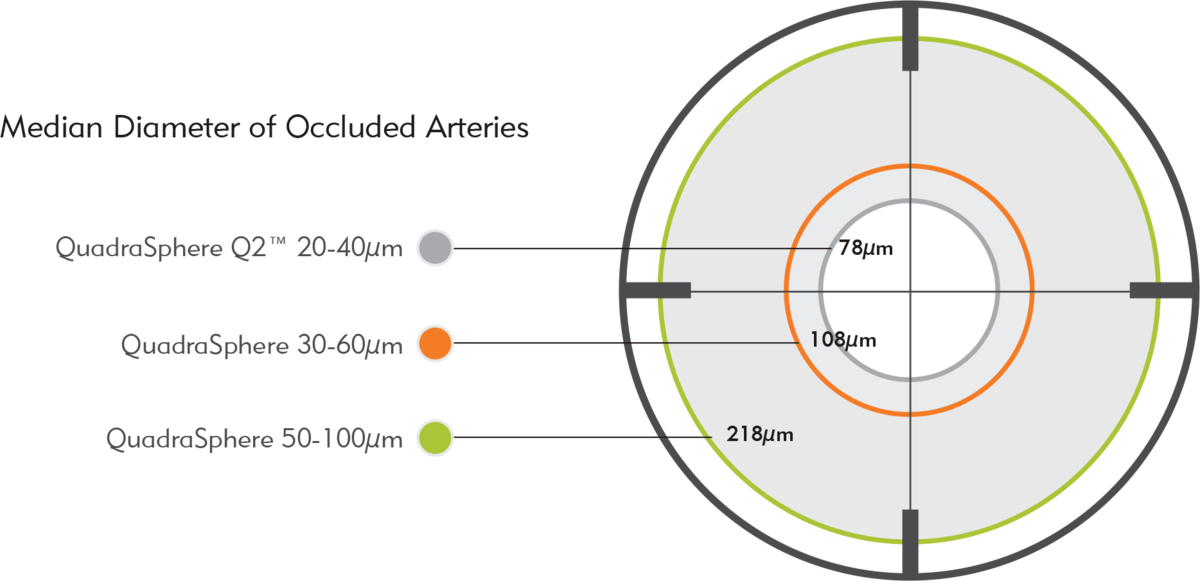

The in vivo median diameter of occluded arteries is significantly different between sizes of QuadraSphere Microspheres,* providing targeted occlusion.

QuadraSphere Q2 Microspheres demonstrate a median occlusion of 78 µm, a statistically significant difference compared to larger sizes of QuadraSphere.

*Swine liver embolization model study performed for Merit Medical. QuadraSphere Microspheres prepared in 50/50 mixture of saline/contrast.